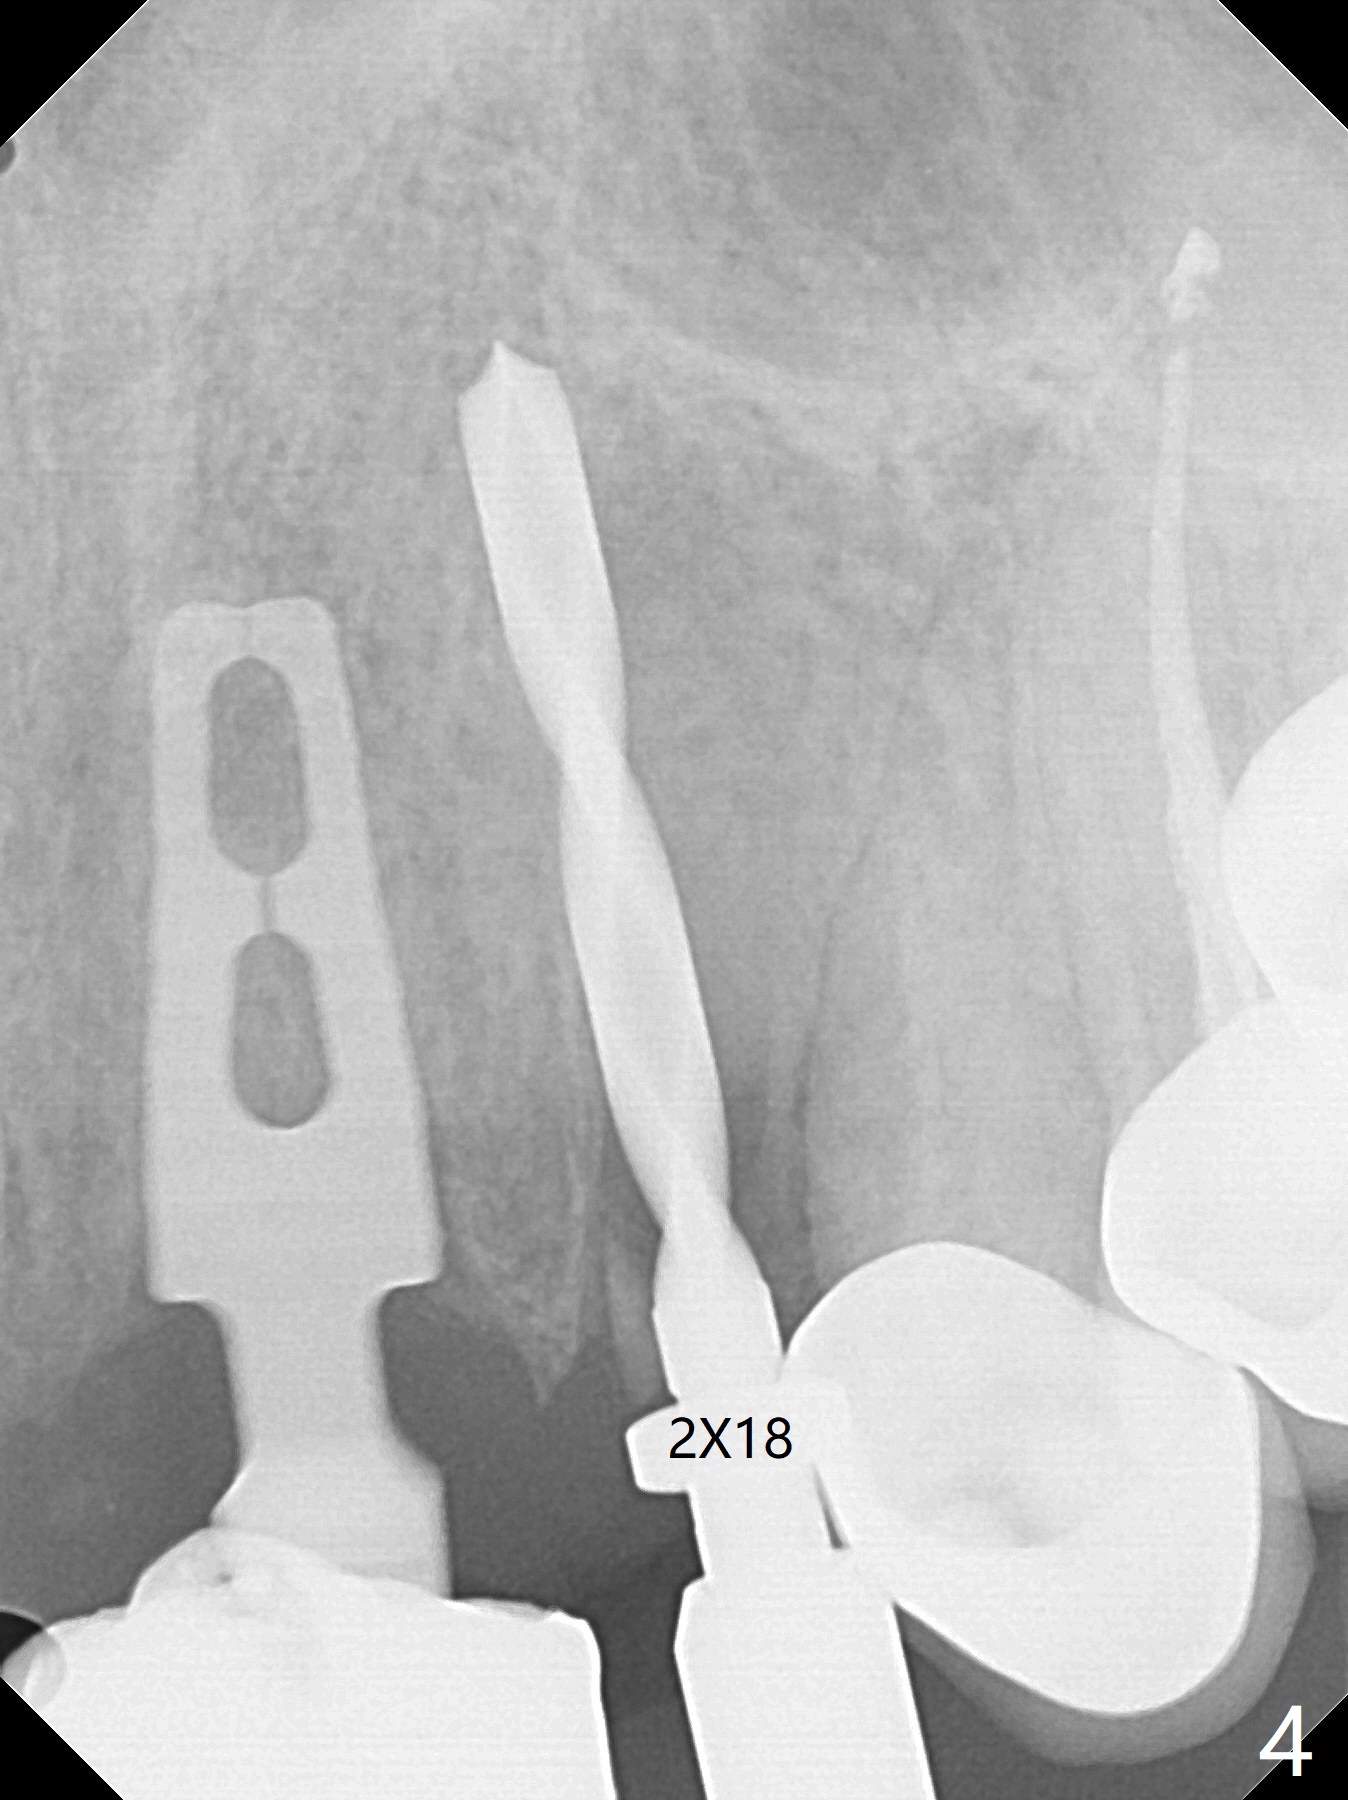

上前牙桥撤除显示右上1,2牙齿以及左上2叶片状植体好像可以保留,而左上3牙齿不能(图一,二(<:托牙边缘压迹)),拔除左上3牙齿后, 暂时把牙桥回位(图三:FPD(已经去除左上3号牙牙冠))作为3号牙种植位置参考(图四至六(G:骨粉))。其实植入前,当最后一个钻头还在原位,将PRF膜和粘性骨放置颊侧根尖(但愿骨粉能放深点),因为那里骨质很薄,好像缺损。由于植体扭力很低(大约5Ncm),放置骨粉覆盖植体(图七),为了不用缝线,涂牙周胶水(图八),放置胶原膜(图九),再涂胶水(图十)固定,最后利用右上1,2号牙(去龋,build-up后)和左上2植体制作临时牙桥,并且覆盖左上3牙槽窝。术后即刻CT显示植体颊侧(B)骨粉(图十一:*)。<:植体根尖仍有间隙,植体应该再长2毫米,初步稳定性会好些。左上3植牙愈合后,将与左上2植体制作左上1-3悬臂桥,右上1,2号牙将做根管治疗,桩,牙冠。临时牙桥术后十一天松动,右上一,二牙牙髓活性测定正常,深洗后,再次build up,不小心把左上3胶原膜吹掉,下面骨粉还稳定。术后三周病人回来做右上六种植,前牙临时修复体(图十二)需要修改(图十三)。拍摄三个方向照片显示前牙牙龈乳头(颊侧和咬合面)。